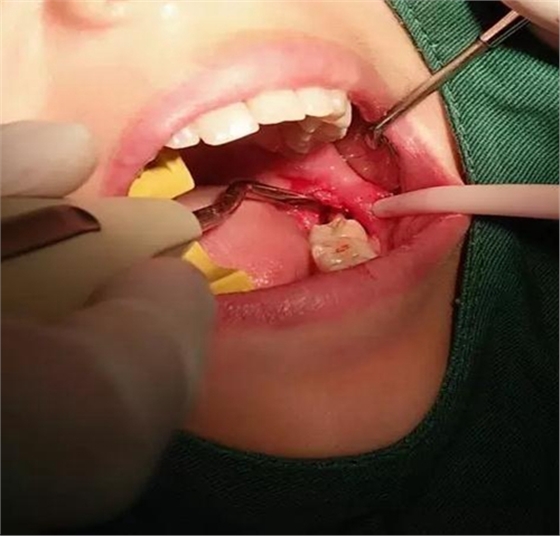

下面看一個(gè)病例,患者,女,30歲,因左下頜智齒嵌塞食物后疼痛,至當(dāng)?shù)匮揽平o予拔除,但術(shù)后1個(gè)半月,患者自覺(jué)拔牙區(qū)一直隱隱疼痛,時(shí)輕時(shí)重,遂來(lái)診。檢查發(fā)現(xiàn),拔牙創(chuàng)口一直未愈合,未見(jiàn)明顯腫脹,拍片發(fā)現(xiàn),拔牙窩內(nèi)顯示高密度斷根影

像,該斷根臨近下頜神經(jīng)管,同時(shí)發(fā)現(xiàn)第二磨牙遠(yuǎn)中有兩塊高密度影像,疑似殘留骨片或牙片,應(yīng)該是引起疼痛的原因,經(jīng)與患者溝通,采納建議,進(jìn)行二次拔牙。

用到4號(hào)牙挺,避免敲擊拔牙根,稍有不慎,可能會(huì)出現(xiàn)牙根移位下頜神經(jīng)管。

挖匙取出